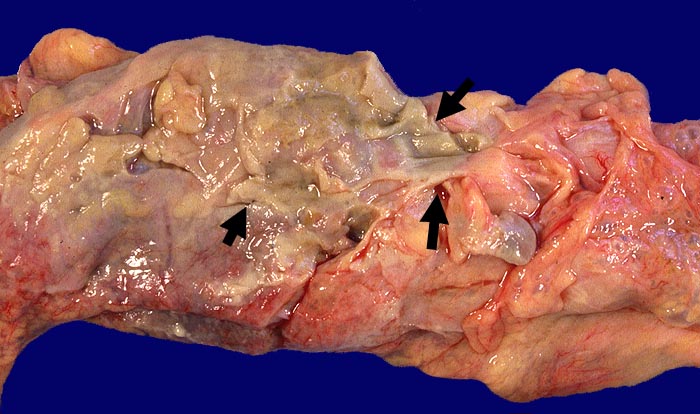

Divertikulitis

Entzündung / Reparatur

Darm, Anus

Kolon Sigma

Makroskopie

Pathologischer Befund